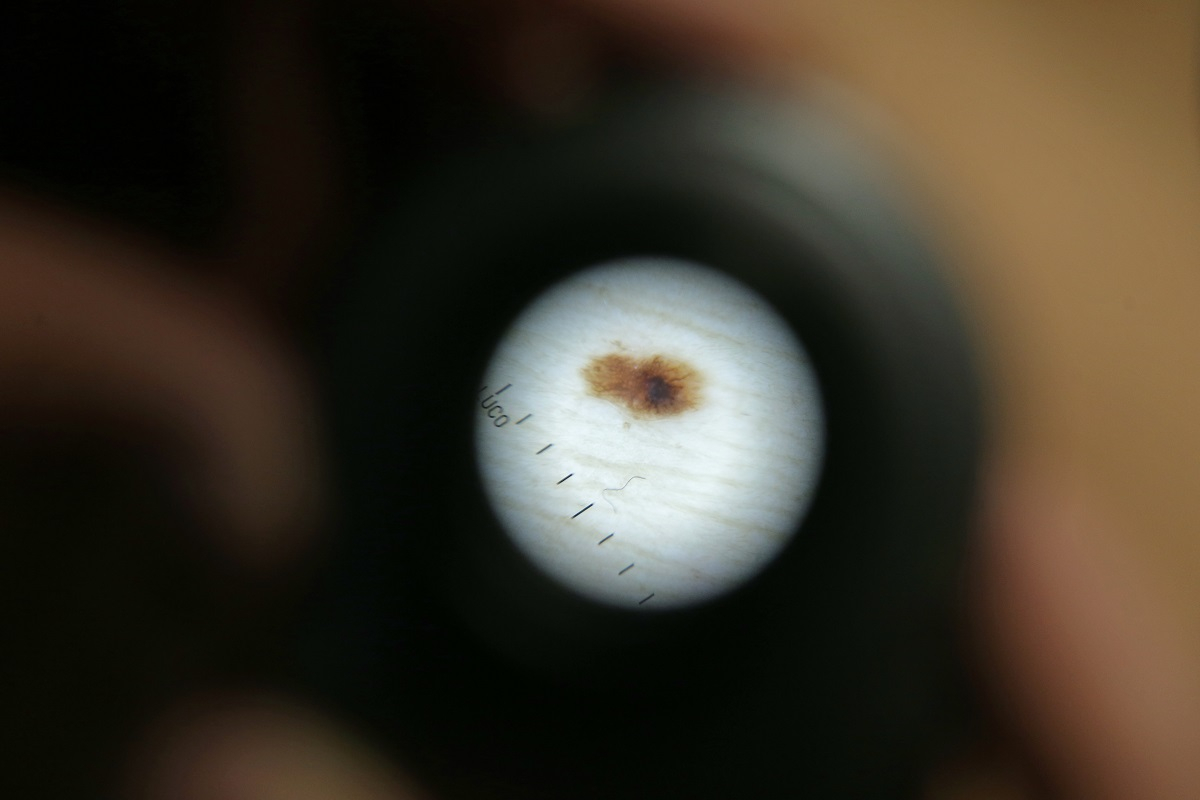

Takto vypadají některá mateřská znaménka pod speciálním přístrojem, dermatoskopem.